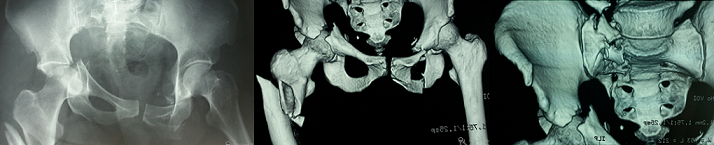

Les fractures ipsilatérales pelviennes et fémorales sont appelées «Hanche flottante». Il y a deux entités lésionnelles selon le type de la fracture pelvienne: fracture de l'anneau pelvien ou fracture du cotyle. Ces traumatismes de haute énergie très peu décrits en littérature posent un problème de hiérarchisation des gestes de stabilisation. Chez les patients présentant une fracture de l'anneau pelvien, la fixation externe doit être faite en premier avant la fixation fémorale car il s'agit souvent de fractures instables et il est essentiel de stabiliser le patient en premier, la fixation externe fournit aussi la stabilité relative de l'anneau pelvien et facilite l'ostéosynthèse du fémur. Par contre chez les patients ayant une fracture du cotyle, les fractures fémorales doivent être fixées en premier pour pouvoir réduire ultérieurement plus facilement le cotyle. Nous rapportons le cas d'une patiente de 35 ans, victime d'une chute du 2ème étage avec point d'impact au niveau de la hanche gauche. Le bilan lésionnel a objectivé des lésions traumatiques graves du bassin, comprenant une fracture du bassin type C3 selon la classification de Tile (lésions antérieures et postérieures avec instabilités rotatoire et verticale + fracture transversale du cotyle), une fracture du sacrum, de l'apophyse transverse de L5, du cadre obturateur controlatéral et une fracture ipsilatérale sous trochantérienne complexe réalisant le tableau de «hanche flottante». Nous avons préconisé d'abord la réduction et l'ostéosynthèse interne de l'extrémité supérieure du fémur (Clou Gama long) puis traitement des fractures du cotyle et du bassin.